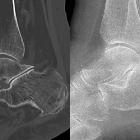

talocalcaneal coalition

Talocalcaneal coalition is one of the two most common sub-types of tarsal coalition, the other being calcaneonavicular coalition. It accounts for 45% of all tarsal coalitions, and although all three facets of the talocalcaneal joint can be involved, the middle facet is most commonly involved.

Plain film findings include:

- C-sign

- best assessed on a lateral ankle radiograph

- posterior continuity of the talus and sustentaculum tali

- sensitivity: 50%

- specificity: 90%

- talar beak sign

- best seen on the lateral ankle radiograph

- prominent beak at the anterior aspect of the talus

Secondary radiographic features that suggest the diagnosis include close apposition of the middle facet of the talocalcaneal (subtalar) joint or non-visualization of the middle articular facet . Sclerosis around the articular margins of the talocalcaneal joint may also occur.